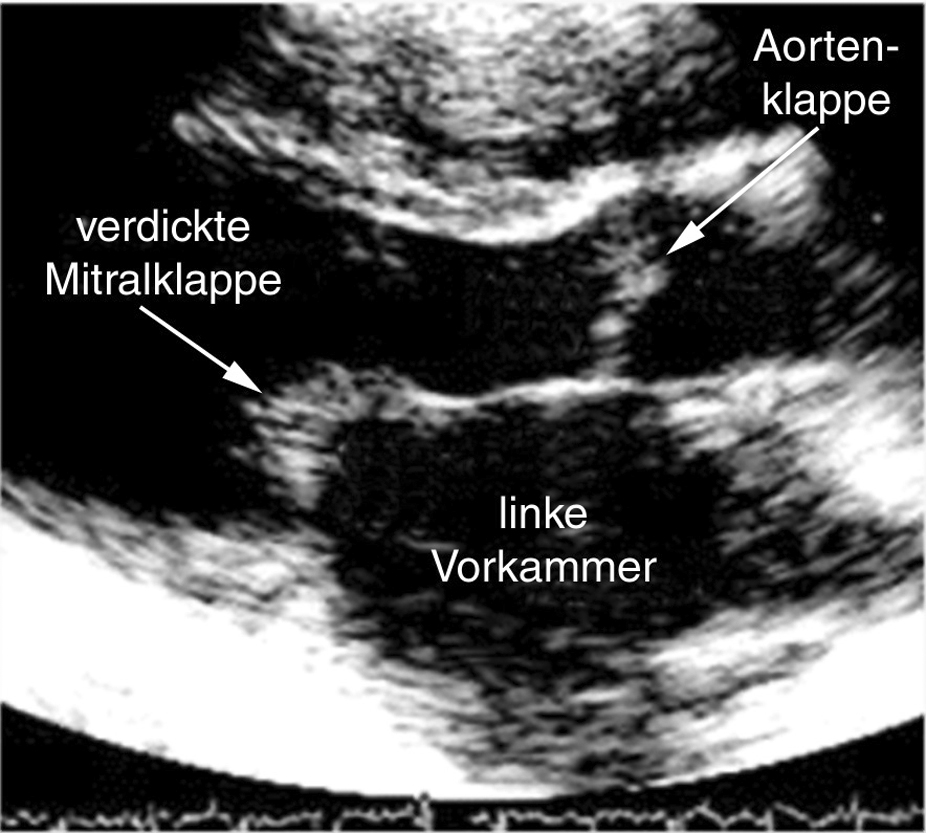

Herzklappen bestehen normalerweise aus dünnen Hautläppchen. Man kann sie im Echokardiogramm als zarte Gebilde erkennen, die sich mit jedem Herzschlag öffnen und schließen (Film 4).

Wenn Herzklappen erkranken verdicken sie sich und verkalken (Abb. 7 und Film 5). Solche plumpen Gebilde können sich nicht mehr richtig öffnen oder schließen.

|  | |

| Abb. 7 | Film 5 |